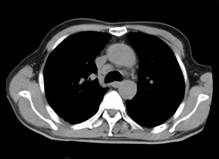

杨××,男,63岁,CT示右肺门占位(图1a~b)经穿刺活检证实右肺门部腺癌、纵膈淋巴结转移,基因检测提示“吉西他滨、5-Fu、铂类”化疗药物敏感;经三次介入治疗后CT(2012年12月19日)复查,瘤体明显缩小,纵膈肿大淋巴结消失(图2a~b);后无特殊治疗,4年后复查(2017年1月8日),病情稳定,瘤体不明显(图3a~b)。